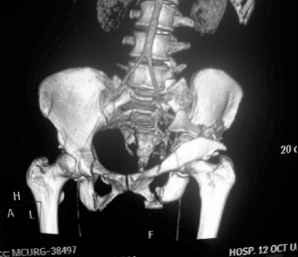

I'm posting this case on behalf of Dr. Pedro Caba, he is unable to post but able to read. 41 yo female , fall from 10 meters five days ago. Hemodynamically unstable on admission treated by angio and embolization and skeletal traction, with no external support. No associated injuries. Based on CT scan the pt has a both column fracture with conminuted dome and displaced anterior column and a sacral Denis 1 fracture with a displaced left ala. I think the best approach for the acetabular fracture is ilioinguinal with Smith-Petersen extension but don't know exactly the sequence . Will you start with the sacral fracture? Which technique? Thanks in advance Pedro Caba Unidad de Trauma Hospital 12 de Octubre Madrid Spain

The soft tissues are also in mild condition, buttock hematoma and probably a Morel-Lavalle. I send some more CT images. There are some conminution in the posterior column (I don’t have images now). The patient is scheduled for surgery next Monday. The plan is percutaneous sacral fixation and then ilioinguinal approach .

This complex and displaced sacral injury is likely an H pattern...2 hemipelvic components, an upper sacral component which remains attached to the lumbar spine, and a caudal sacral component...there are typically anterior ring injuries as well...in this patient's example, the left sided acetabulum also has been exploded.

Most H pattern sacral fractures have the transverse fracture limb of the "H" at the upper-second sacral segment junction or disc region...some fracture thru the second segment, and some or at other sites...but most yield thru the upper-second sacral segments junction...with variable traumatic associated neurological findings.

The hemipelvic components' displacements depend on their instability...this patient's left side seems to be the worst.

The transverse fracture limb liberates the upper sacral segment and its attached lumbar-thoracic-cervical spine to displace...usually anteriorly and in kyphosis.

The kyphosis and anterior translation of the upper sacral segment distorts the safe area for iliosacral screw usage...the imaging allows the surgeon to preoperatively plan if iliosacral screw fixation is a safe possibility.

For this patient (according to the limited imaging available), it would seem that a combination of lumbo-pelvic fixation along with transiliac transsacral fixation is optimal...BUT the left sided pelvic implants must be applied in consideration of and in anticipation of the necessary acetabular fixation implants.

So you are correct, this pattern likely needs a great reduction and a powerful fixation construct to be durable...but the operative exposure and implants must be planned carefully if the acetabular fracture is to be accurately reduced and well stabilized.